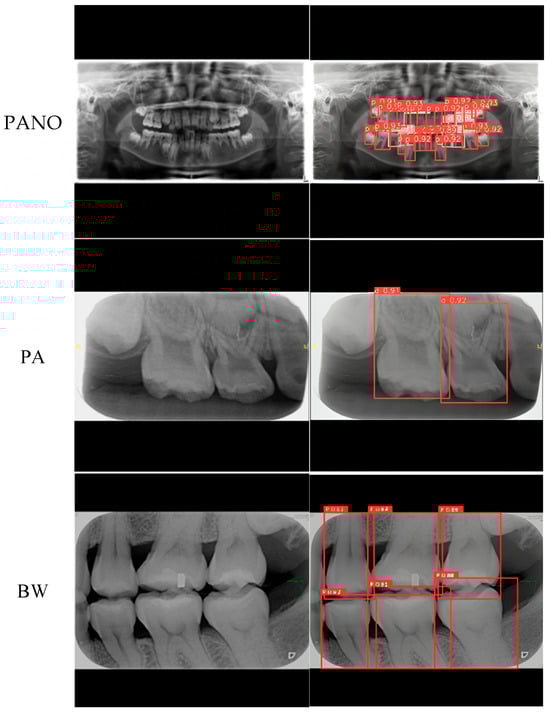

| PANO | Precision ↑ | 95.90% | 89.69% | 97.01% | 93.13% |

| Recall ↑ | 98.65% | 94.27% | 99.22% | 96.50% | |

| PA | Precision ↑ | 79.44% | 83.80% | ||

| Recall ↑ | 95.00% | 95.37% | |||

| BW | Precision ↑ | 95.21% | 96.83% | ||

| Recall ↑ | 99.24% | 99.56% | |||